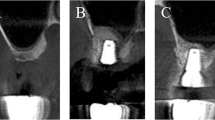

Histolomorphometricly new bone formation was similar − 27.7 ± 15% vs. 32.1 ± 19%. (block vs. particles respectively) (Figs. 1, 2).

Despite the fact that particulate bone substitutes may achieve good results when used in sinus augmentation in general, bone-block allografts may offer more structural benefits in extremely atrophic cases (residual alveolar ridge height ≤3 mm), and can be shaped to match the host site6. In addition, block grafts may improve primary stability, advantageous for proper osseointegration and simultaneous implant placement21 (Fig. 3).